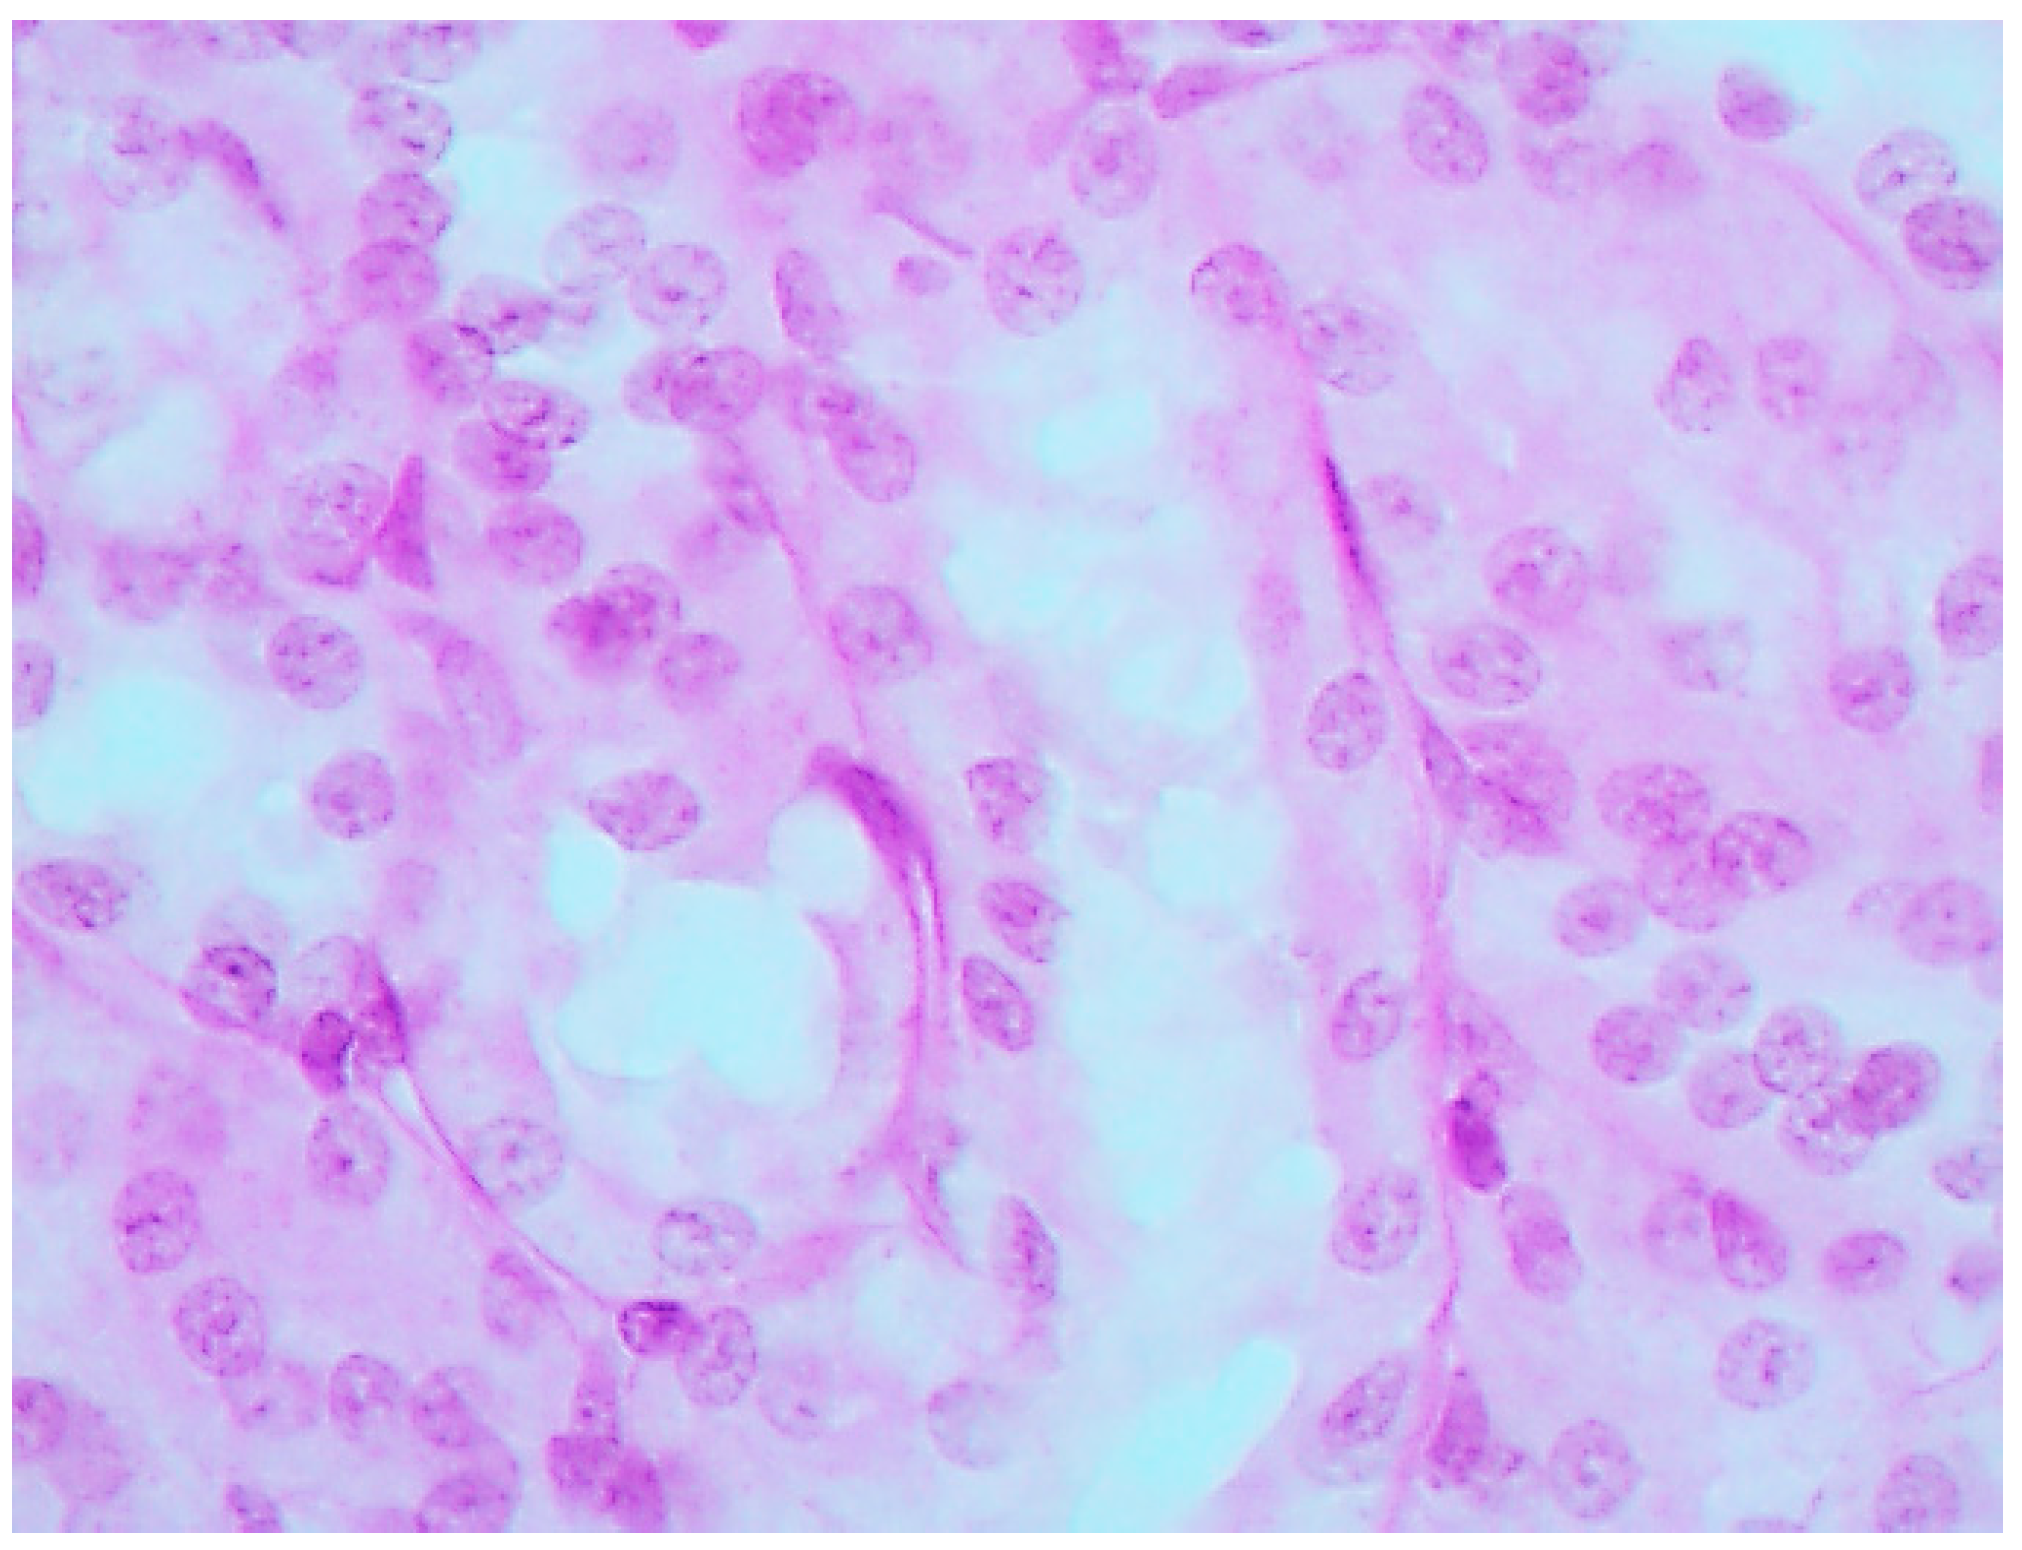

The histological picture (Figure 2, Figure 3 and Figure 4) and morphometric characteristic (Table 4) of the epithelium in the proximal convoluted tubules provide evidence of marked damage, which is a little more marked in response to NiO-NPs and, particularly, Mn3O4-NPs + NiO-NPs, than to Mn3O4-NPs alone, but is absent for the same combined intoxication with the background administration of the BPC.

Figure 3. Kidney of a rat exposed to nanoparticles of NiO and Mn3O4 together. Marked degenerative and necrobiotic changes of tubular epithelial cells up to their disappearance; partial destruction of the brush border. PAS stain, magnification ×400.

Ijms 16 22555 g003

The most prominent and similar pathological changes of brain structures were revealed in the area of caudate nucleus and in the CA1 area of the hippocampus; as examples, we give microscopic pictures of the latter in a control rat (Figure 5) and in one exposed to Mn3O4-NPs + NiO-NPs (Figure 6) Both morphometric indices of the brain’s histological picture used in our study, namely, counts of neurons with completely absent nucleolus and of those with a distinct nucleolus located in the nucleus centre show substantial damage to these structures of the brain mostly in the rats exposed to either Mn3O4-NPs or Mn3O4-NPs + NiO-NPs. This adverse effect is almost absent in rats exposed to the same toxic combination with the background BPC administration (Table 6 and Figure 7).

Figure 5. The brain of a control rat, hippocampus (CA1). Hematoxylin and eosin stain, magnification ×400. The neuron nuclei are predominantly spherical with well-visible eosinophilic granulosity, and notable nucleoli in the center.

Figure 6. The brain of a rat exposed to nanoparticles of NiO and Mn3O4 together; hippocampus (CA1). Hematoxylin and eosin stain, magnification ×400. A lot of neurons with marked degenerative changes or pycnosis; in some nuclei the nucleolus is displaced or absent.